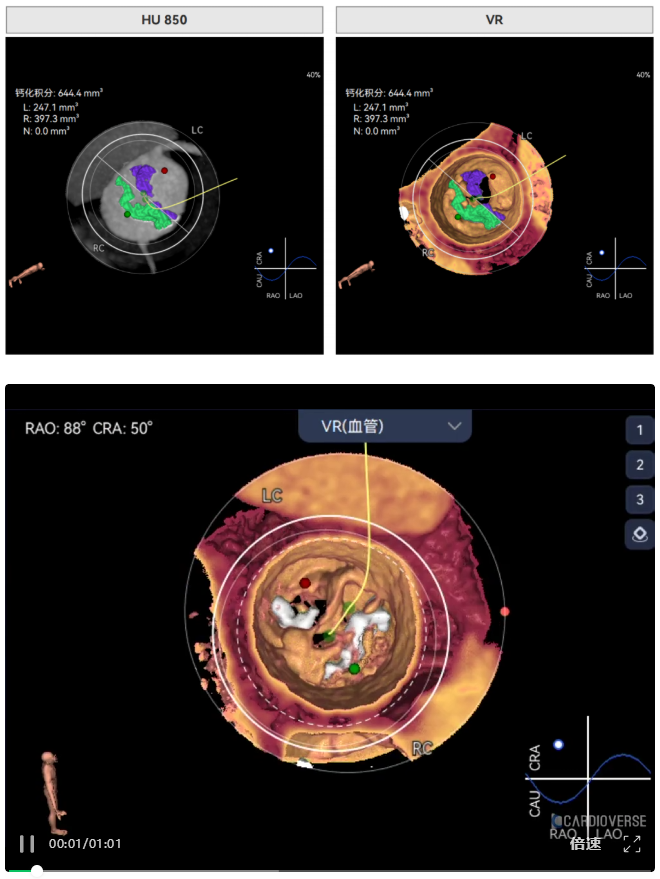

主动脉瓣环周长径18.4mm,极小瓣环,LVOT直筒型结构;Type0型二叶瓣,鱼嘴处最窄预估宽度16.9mm。心脏角度34°,窦部空间大,无冠脉风险。

HU850钙化积分644,中重度钙化,瓣上限制较重,对瓣膜径向支撑力有一定要求,自杀左室,术前合并轻度反流,有一定循环崩溃风险。